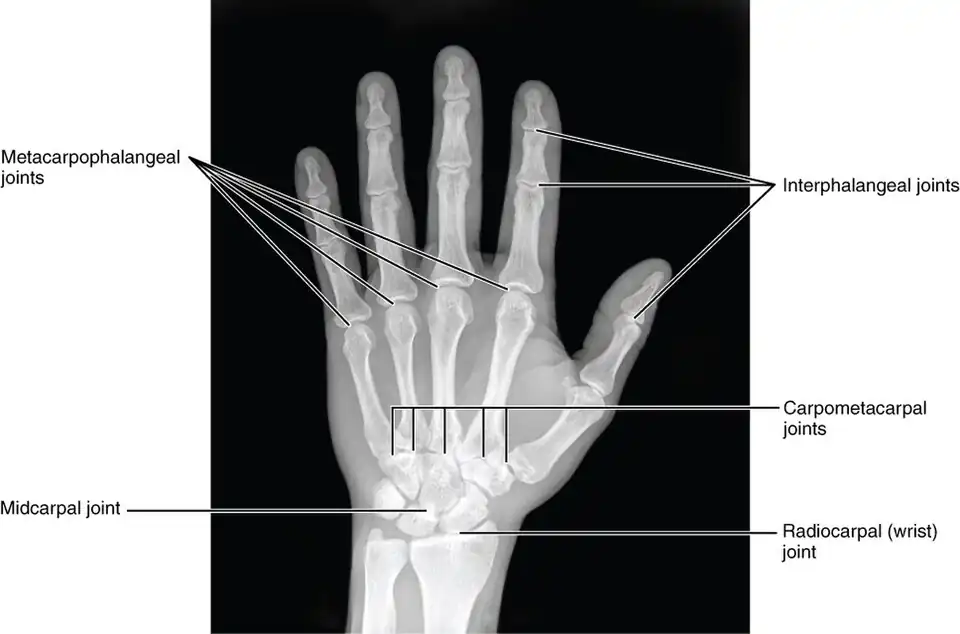

The skeleton of the human hand consists of 27 bones:[10] the eight short carpal bones of the wrist are organized into a proximal row (scaphoid, lunate, triquetral and pisiform) which articulates with the bones of the forearm, and a distal row (trapezium, trapezoid, capitate and hamate), which articulates with the bases of the five metacarpal bones of the hand. The heads of the metacarpals will each in turn articulate with the bases of the proximal phalanx of the fingers and thumb. These articulations with the fingers are the metacarpophalangeal joints known as the knuckles. At the palmar aspect of the first metacarpophalangeal joints are small, almost spherical bones called the sesamoid bones. The fourteen phalanges make up the fingers and thumb, and are numbered I-V (thumb to little finger) when the hand is viewed from an anatomical position (palm up). The four fingers each consist of three phalanx bones: proximal, middle, and distal. The thumb only consists of a proximal and distal phalanx.[11] Together with the phalanges of the fingers and thumb these metacarpal bones form five rays or poly-articulated chains.

The articulations are:

- interphalangeal articulations of hand (the hinge joints between the bones of the digits)

- metacarpophalangeal joints (where the digits meet the palm)

- intercarpal articulations (where the palm meets the wrist)

- wrist (may also be viewed as belonging to the forearm).

Additional images

-

X-ray showing joints

X-ray showing joints -

Hand bone anatomy